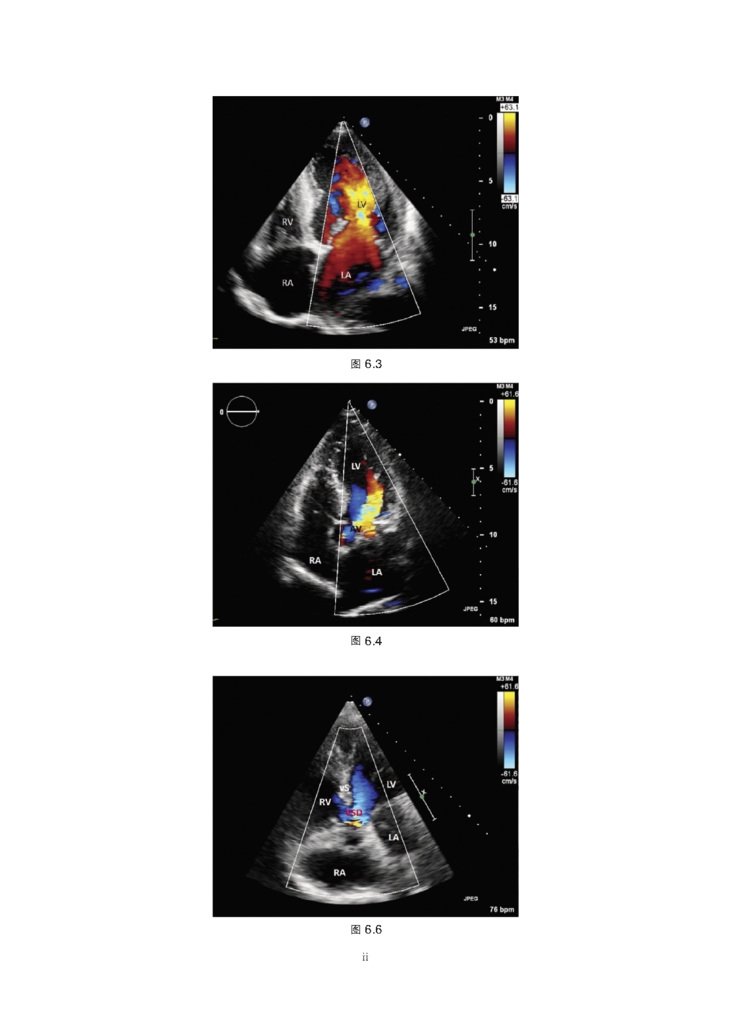

本书为心脏病学临床指导性用书,主要从体格检查、患者主诉分析、常见心血管疾病分类、辅助检查、介入治疗及药物治疗6部分对临床心血管疾病诊疗进行了系统介绍,各章辅以要点、图表和流程图等形式阐释了心脏病学的基本概念和重要临床表现,是一本适用于广大心血管内科医生和医学生的案头必备书。

2.涵盖常用检查技术、常见疾病、影像学方法(包括胸片、MRI和CT)、介入治疗和药物。